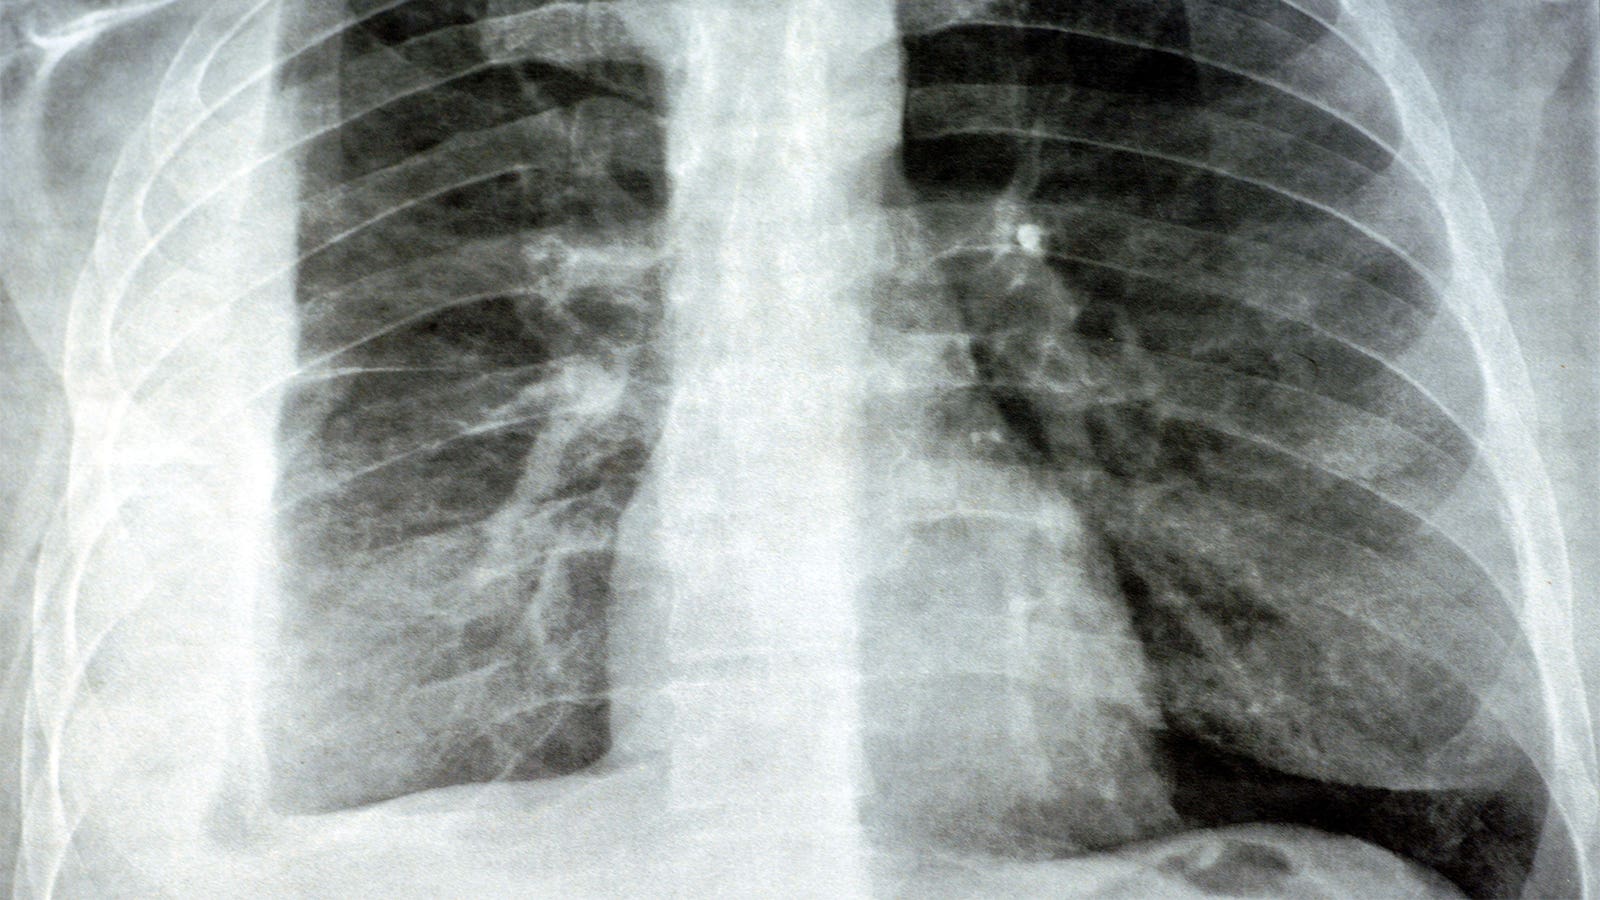

In a recent retrospective cohort study conducted across 18 hospitals in Canada, researchers found that antibiotic therapy with extended anaerobic coverage (EAC) did not offer any survival benefit to patients with community-acquired aspiration pneumonia. This study, led by Anthony Bai, MD, MSc, of Queen’s University, revealed that there was no significant difference in mortality rates between patients treated with EAC compared to those receiving limited anaerobic coverage (LAC).

Overall, the study sheds light on the changing landscape of pneumonia treatment and the need to reevaluate the strategies employed to combat this respiratory condition. By focusing on evidence-based practices and avoiding unnecessary broad-spectrum antibiotic use, healthcare providers can optimize patient outcomes and reduce the risk of complications associated with aspiration pneumonia.